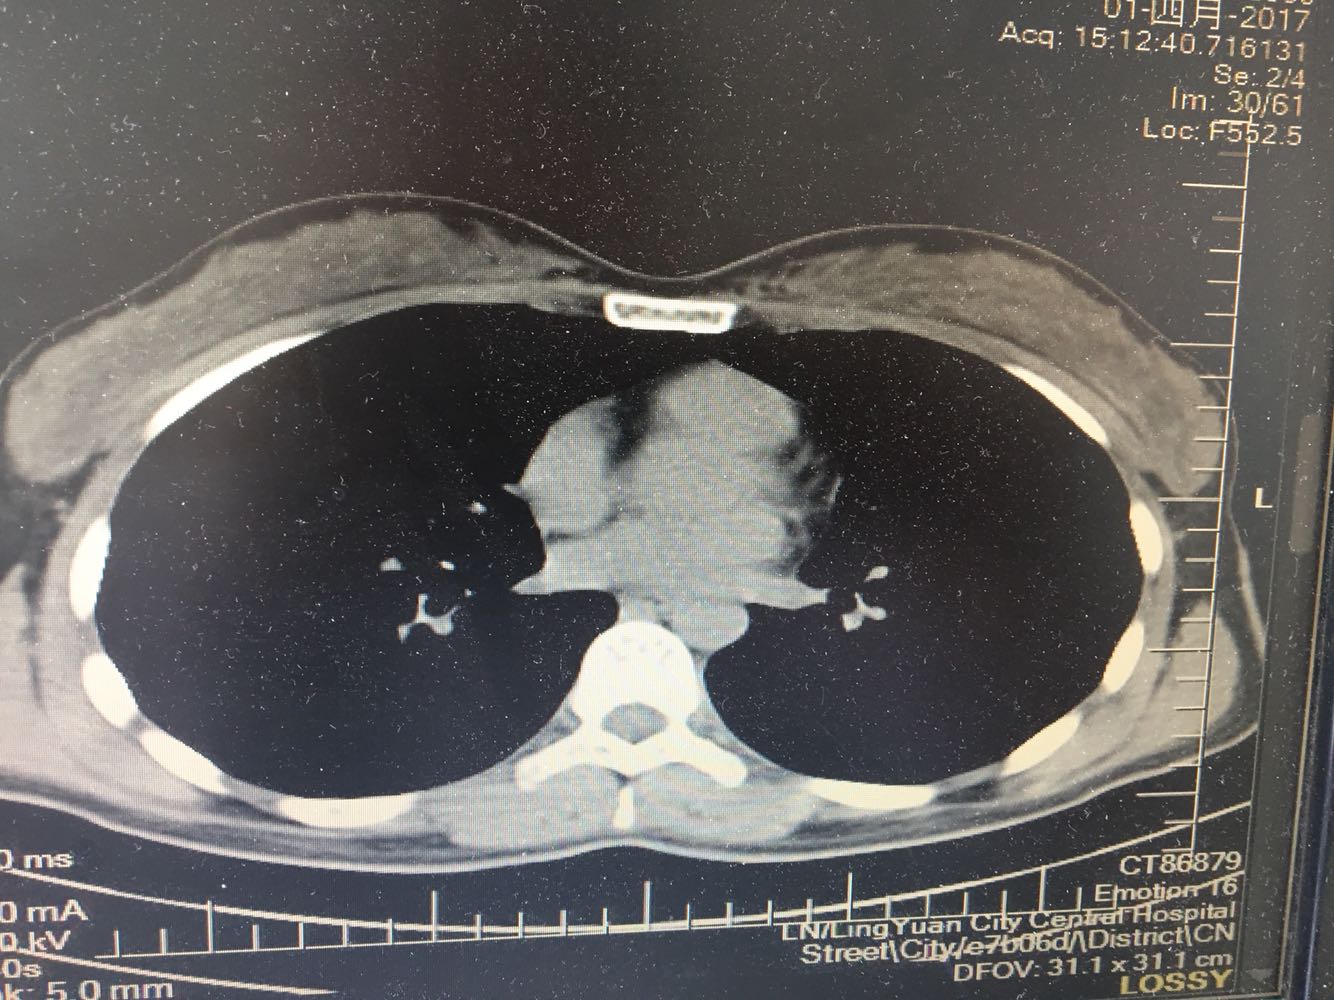

女,26岁,咳嗽1周,咳痰不畅,咽喉痒,口服阿莫西林无好转,昨日发热,体温38.5摄氏度,于门诊查肺CT后以肺炎收入院,病来无盗汗,无咳血,无消瘦及乏力,无头痛,无肢体酸痛,饮食睡眠可,二便正常

神清言明,咽部无充血,扁桃体不大,双肺呼吸音清,无罗音,服软无压痛。

支原体肺炎?肺结核?

支原体抗体1:160,结核抗体弱阳性。支原体肺炎个别可见上叶病变,该患无结核中毒症状,考虑支原体肺炎可能性大,但肺尖为结核好发部位,需要抗炎治疗后复查观察疗效。